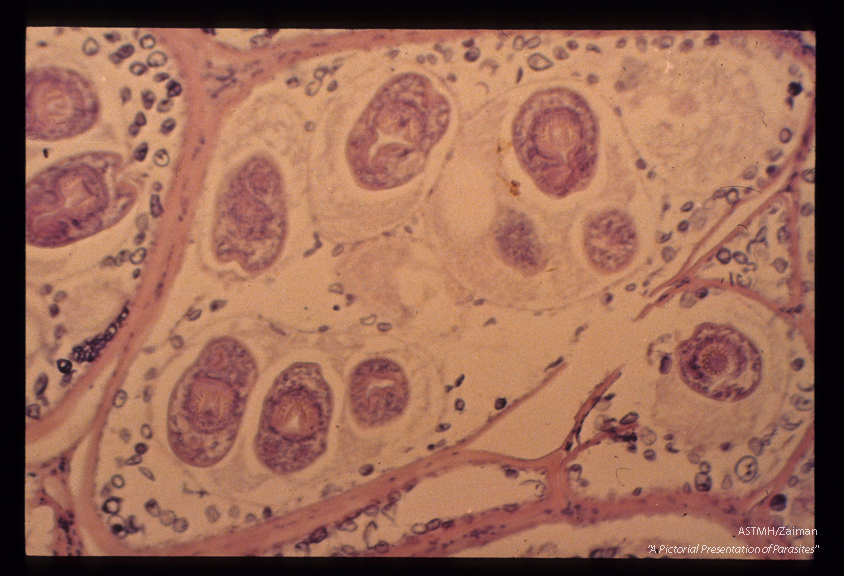

Thanks to the generosity of Herman Zaiman and his family, ASTMH proudly presents “Pictorial Presentation of Parasites,” a famous collection of more than 2,000 slides of various vectors.

His "Pictorial Presentation of Parasites" is a seminal image collection that will remain a valued resource for those in the tropical medicine and hygiene field for decades to come.